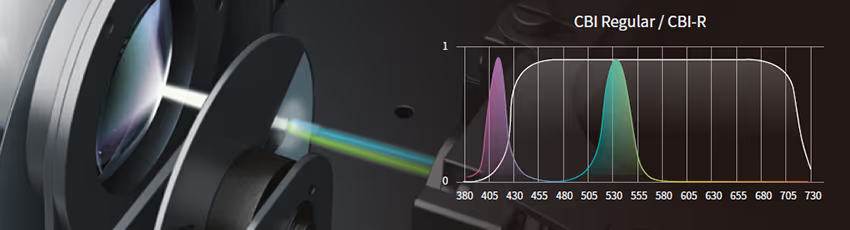

Bileşik bant görüntüleme teknolojisi, endoskopi sırasında sindirim sistemini incelemek için doku özelliklerini kullanır.

Güçlü algoritmalar, klinik gözlem ve tanıyı kolaylaştırmak için üç modda görüntü ayrıntılarını geliştirir.